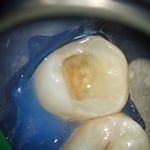

写真はすべてミラー像です。上顎左側側切歯遠心面の大きな虫歯です。エキスカで丁寧に軟化象牙質を除去していくと、歯髄腔まで本当に皮一枚になりました。血流が見えるようです。エキスカから伝わる組織の硬軟の感覚と対物-接眼レンズからの像が ”皮一枚”を達成できたと思います。皮一枚ですが、硬組織は残っていますので、ティース・プライマーを塗布し、スーパーボンド・ラジオオペークとバルクベースにて覆髄をしました。もちろん、1ケ月後の歯髄診でも陽性反応を示し、歯髄は生きています。